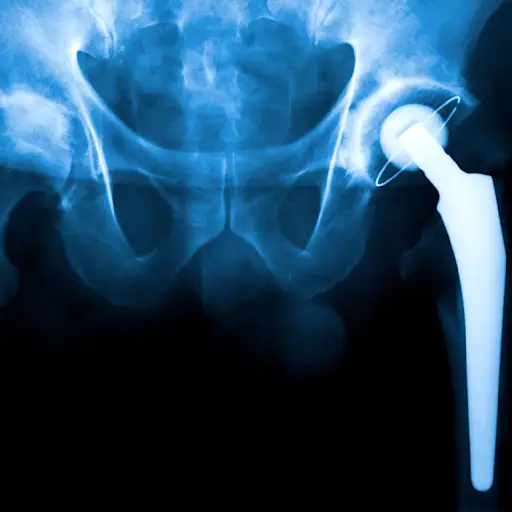

什么时候我应该考虑关节置换手术?

“关节置换是一项选择性手术,”坎贝尔医生说,“所以我告诉我的病人,这是一个关乎生活质量的决定。”他说,你的x光片可能会显示严重的关节损伤,但如果你感觉良好,能够正常工作,做你喜欢的事情,没有必要急着做手术。“当疼痛和功能障碍限制了人们的活动,并对生活质量产生了负面影响,而你的非手术选择失败时,你就该考虑这个问题了。”与你的医生交谈是第一步。

关节置换术有哪些风险?

首先是一些好消息:塔迦尔医生说,关节置换手术通常非常成功,可以减轻疼痛,恢复关节功能。但和所有手术一样,这也不是没有风险的。他说,最大的问题是持续性的僵硬和与植入物相关的风险,比如植入物松动或感染。“大约有5%到7%的并发症发生率,所以人们似乎总体上做得很好。”其他需要考虑的事情包括手术费用、恢复时间和术后物理治疗——所有这些都可以和你的医生讨论。

我的新关节能维持多久?

最好的答案医生现在可以给予:比以前持续的联合更换更长。“Materials that we’re using now are better than ever, but we haven’t put them in for that long yet so we can’t tell people exactly how long it will last,” Dr. Sutter says, adding that the majority of knee replacements will last for 20 to 25 years. With the way technology has advanced so far, it’s not unrealistic that we’ll see joint replacements lasting for 30 years or more in the neat future, he says.

我必须等到我是在一定的年龄才能进行手术吗?

萨特说,不需要,对关节置换手术没有具体的年龄要求,但患者越年轻,就必须更多地考虑关节的未来。大多数人都不想在一生中进行多次关节置换手术,所以这是一个权衡早期手术利弊的问题。塔迦尔博士补充说:“过去,关节手术是为老年人做的,但由于目标是保持生活质量,而不是恢复生活,所以越来越多的年轻人接受这种手术。”